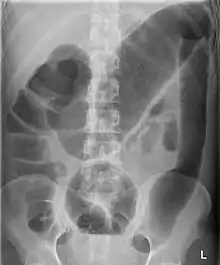

Toxic megacolon associated with ulcerative colitis.

Toxic megacolon

Toxic megacolon is mainly seen in ulcerative colitis and pseudomembranous colitis, two chronic inflammations of the colon (and occasionally, in the other type of inflammatory bowel disease, Crohn's disease). Its mechanism is incompletely understood. It is probably due to excessive production of nitric oxide, at least in ulcerative colitis. The prevalence is about the same for both sexes.